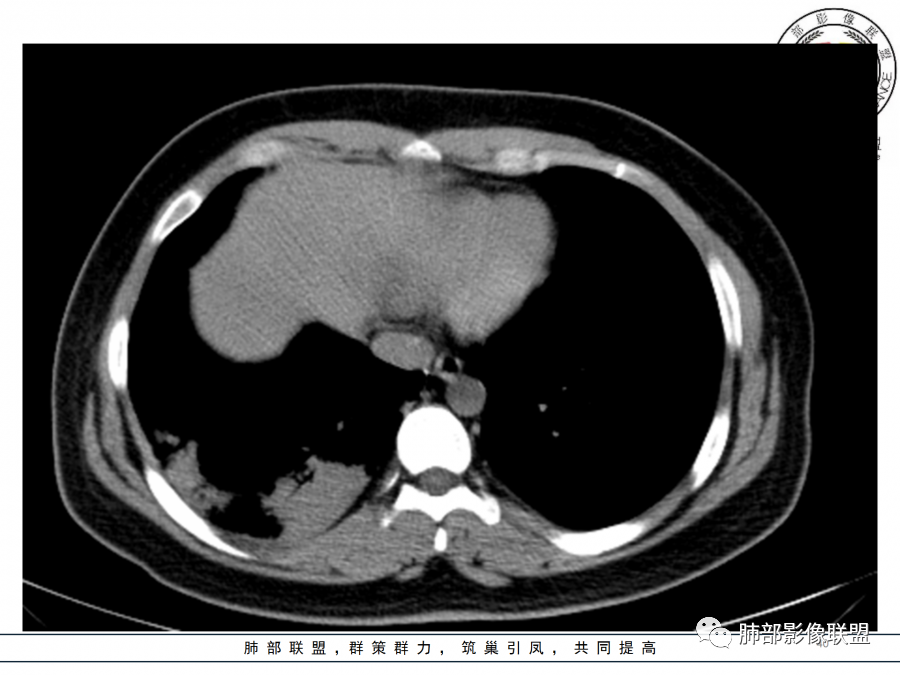

年轻女性,急性病史,发热,WBC17.42*10^9/L,NE%82.8%,

痰革兰染色示:G-杆菌1+、G+球菌1+,未检出真菌,抗酸染色阴性。

大片实变影

细菌性感染?隐球菌?结核?梗死?

淋巴瘤?肺炎型肺癌?支原体?病毒?

1.年轻女性,咳嗽、发热(38.8°),起病急,血象高。影像上大片实变影为主,一般会首先考虑细菌性肺炎,尤其是肺炎链球菌感染等。疗效不满意时考虑其他。

2.影像上怀疑其他病灶的理由有:

1)实变影为大小不等多中心性。

2)沿胸膜下分布趋势(不同于大叶性肺炎的肺叶“造型”)。

3)周围较大范围磨玻璃影及小叶间隔增厚。

4)病灶体积增大明显(叶间裂推移)。

3.腺病毒肺炎可以符合上述改变:实性密度,间质分布为主等。

4.隐球菌感染可以符合上述改变:胸膜下多中心实变密度为主,磨玻璃晕等。但隐球菌临床症状大多隐匿、迁延,影像变化缓慢。

5.本例患者血象高,影像渗出明显,尚不能排除混合感染可能。